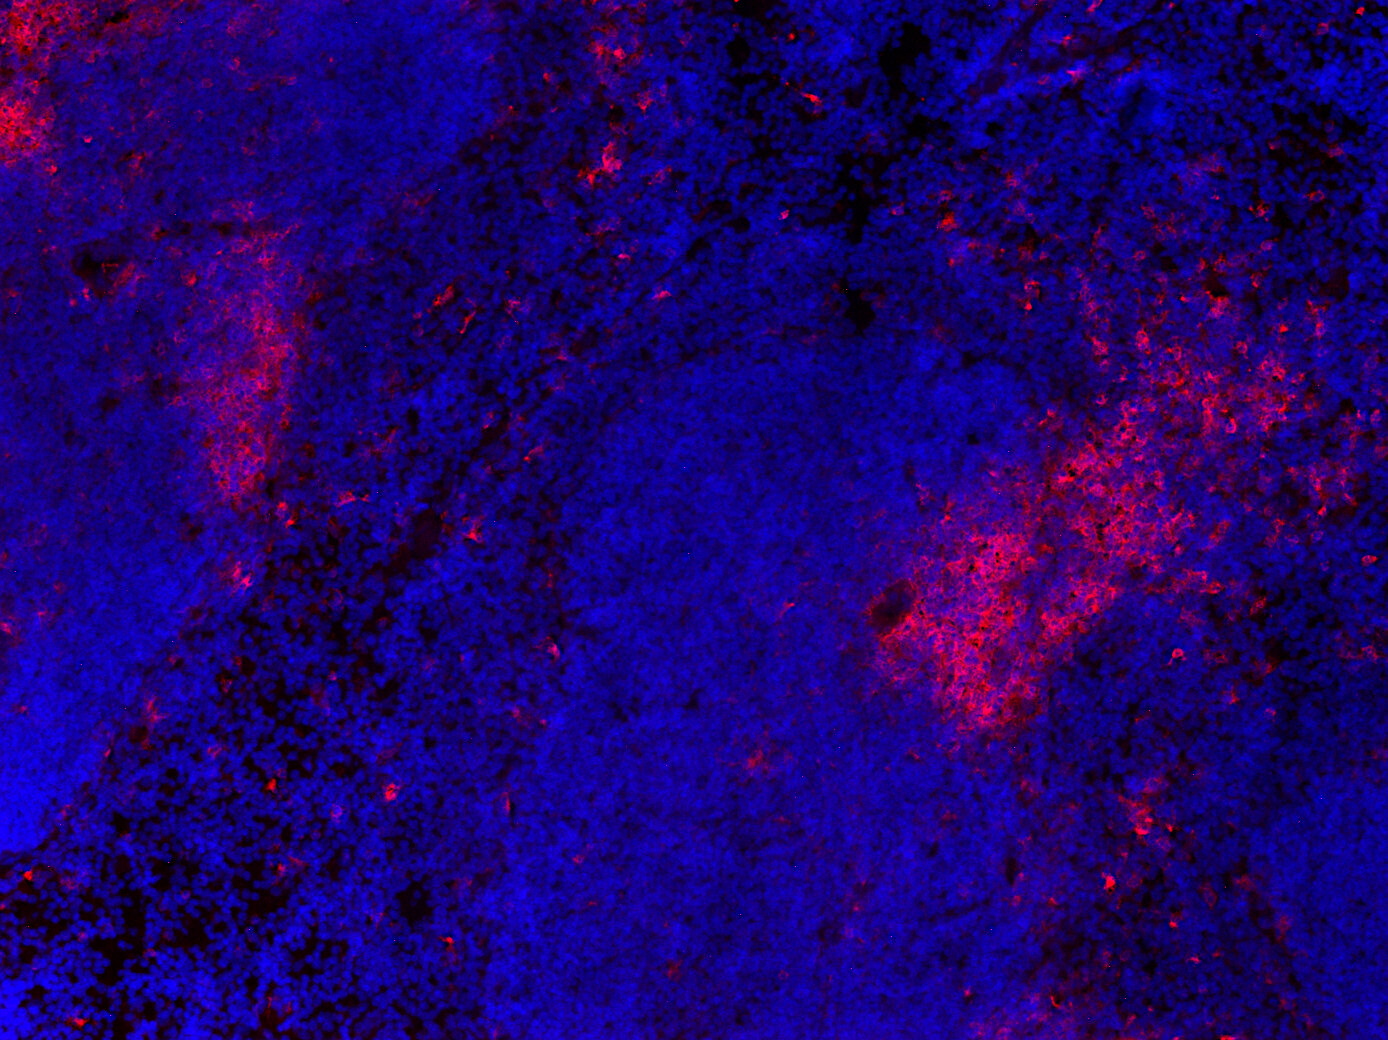

IHC: 1 : 500 gallery

IHC-Fr: 1 : 500 gallery

Immunohistochemistry (IHC) on 4% PFA perfusion fixed tissue with 24h PFA post fixation. Immunoreactivity is usually revealed by fluorescence or a chromogenic substrate. Some antibodies require special fixation methods or antigen retrieval steps. For details, please refer to the ”Remarks” section.

Immunohistochemistry on fresh frozen (IHC-Fr) cryo-tissue-sections. In contrast to standard PFA perfusion fixed tissues, fresh frozen cryo-tissue-sections can be variably postfixed with alcohols, acetone or PFA. Alcohol or acetone fixation is e.g. of advantage for antigens masked by PFA crosslinking. For recommended postfixation, please refer to the ”Remarks” section. Immunoreactivity is usually revealed by fluorescence or a chromogenic substrate.

IHC: Antigen retrieval with citrate buffer pH 6 is required.

IHC-Fr: 4% formaldehyde/PFA fixation is recommended.